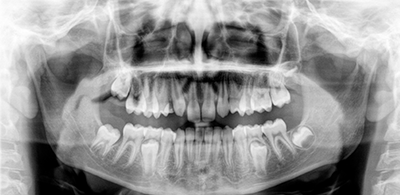

Cirurgias dentárias e

dos maxilares

Cirurgia Ortognática e das

Deformidades dento-maxilo-faciais

Reconstrução da ATM sem uso de próteses metálicas